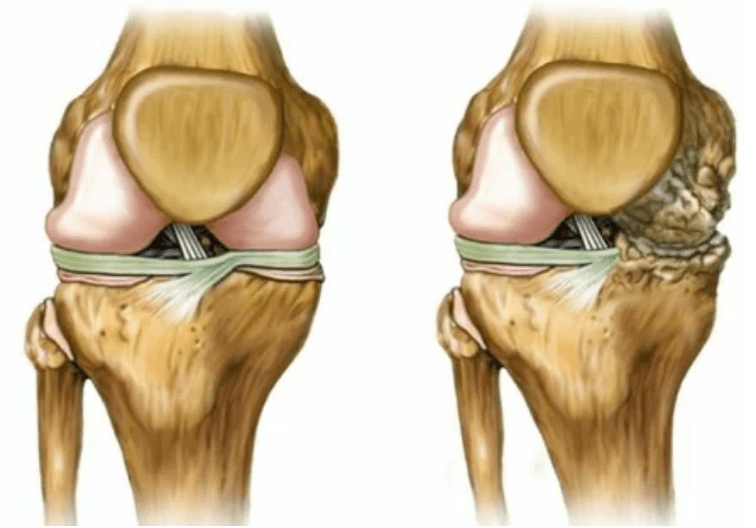

- Level 2. Due to the lack of pension, the necessary cartridges are destroyed.Bone growth is formed on the surface of the cartilage.The pain acquired a more pronounced character, reinforce themselves after a long break and are eliminated by small physical work.Pain is accompanied by inflammation.The muscles are stretched, which leads to weak or average impairments of the motor functions.

- 3 degrees.There is often pain, it is difficult to move the limb due to changes in the joint.The lesions are extensive and are noticeable for the bare look.The deformation of the joint position occurs, the affected area swells and becomes red.The limb axis is disturbed, which leads to the complexity of the movement.The ligaments produce pathological changes.Subbluishes and contractures appear.The adjacent muscles are shortened or stretched from which the contractile function is weakened.